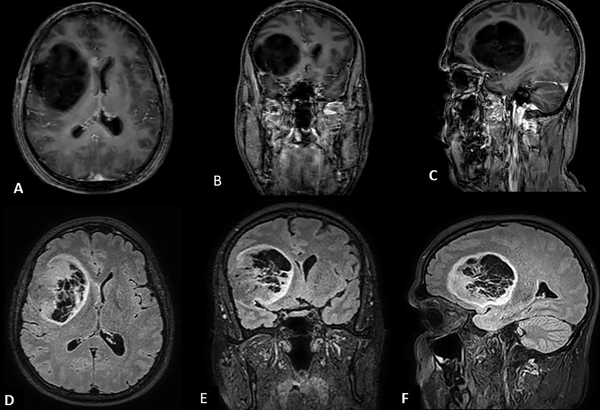

En estudio de resonancia magnética (RM) cerebral con gadolinio (Fig. 1 A, B y C) se define una lesión quística frontal derecha que mide 7.08 cm, x 6.10 cm x 5.28 cm, ocupando un volumen de 114 cm3; presencia de escaso edema perilesional; no se observan realces tras la administración del contraste. En el interior de la lesión se aprecian tabiques intraquísticos que tampoco captan contraste. En secuencia FLAIR (Fig. 1 D, E, F) se puede apreciar aumento en la intensidad de señal en todo el borde de la lesión (“signo del anillo”) y a nivel del entramado trabecular.

Fig.1. Resonancia magnética prequirúrgica, secuencia T1 gadolinio, vista axial (A), coronal (B) y sagital (C). Secuencia FLAIR, vista axial (D), coronal (E) y sagital (F), con el signo del anillo.